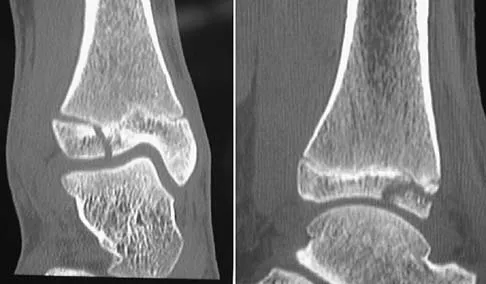

A 28-year-old professional dancer reports a 3-month history of progressive pain in the posterior aspect of the left ankle. Her symptoms are worse when she assumes the en pointe position. Examination reveals tenderness to palpation at the posterolateral aspect of the ankle posterior to the peroneal tendons which is made worse with passive plantar flexion. There is no nodularity, fluctuance, or tenderness of the Achilles tendon. The neurovascular examination is unremarkable. A lateral radiograph and MRI scan are shown in Figures 16a and 16b, respectively. Management should consist of